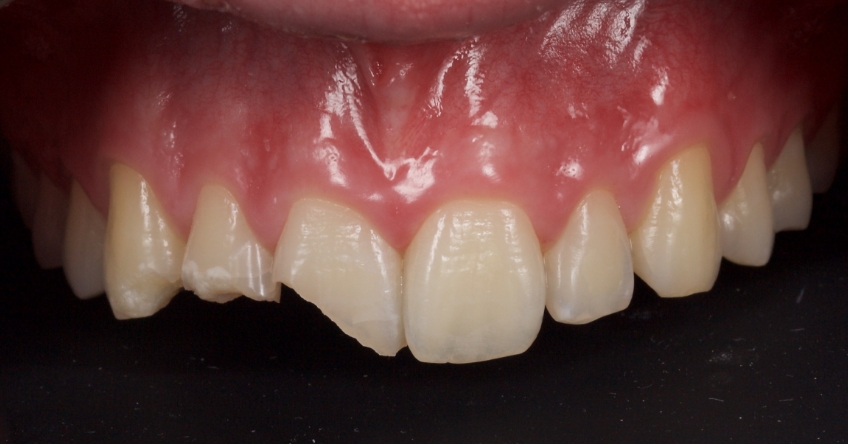

This 21-year-old male presented with an uncomplicated enamel-dentin fracture of the upper right central, lateral incisor, and canine following a fall.